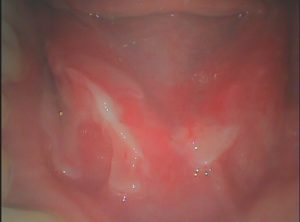

2年前から口腔粘膜の水疱形成と水疱が破れた後の接触痛が続いていました。血液検査(BP180、デスモグレイン)、病理組織学的検査では異常を認めませんでした。酢酸亜鉛水和物(ノベルジン)、当帰芍薬散温清飲、半夏瀉心湯を内服し、1年後には症状が生じなくなりました。